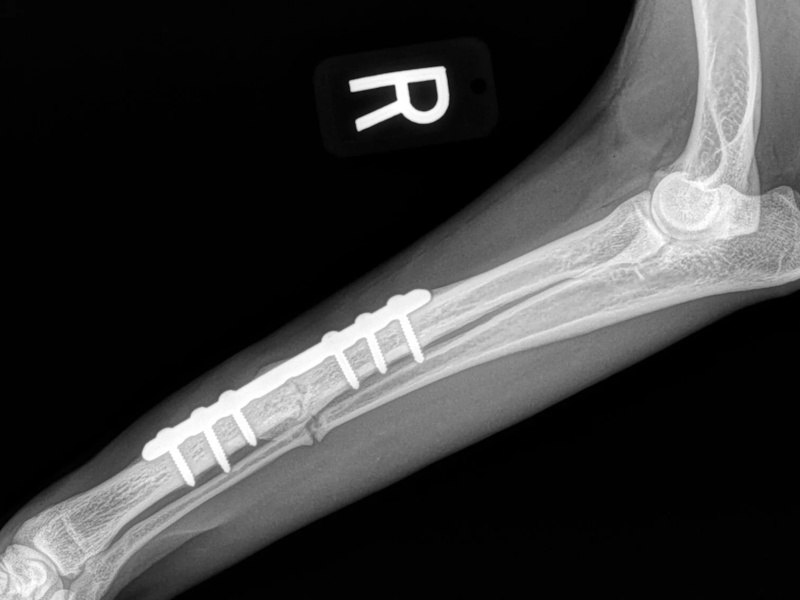

Tibial Plateau Leveling Osteotomy (TPLO) - additional information

An osteotomy is a surgical cut in a bone. In the cruciate deficient stifle, a cut is made in the top of the tibia. The top portion of bone that contains the articular surface is rotated to level it. The two pieces of bone are held in place with a metal plate and screws.

Post Surgical Radiographs

While the patient is still anesthetized, the patient is taken into radiology for post-surgery radiographs (X-rays). The radiographs are assessed to measure the new tibial plateau angle. We are aiming for 5-6 degrees relative to the long axis of the tibia. The apparatus (plate and screws) are assessed for size and appropriate position.

Fore Limb (Humerus, Radius/Ulnar, Metacarpus)

Hind Limb (Pelvis, Femur, Patella, Tibia/Fibula, Lateral Malleolus)